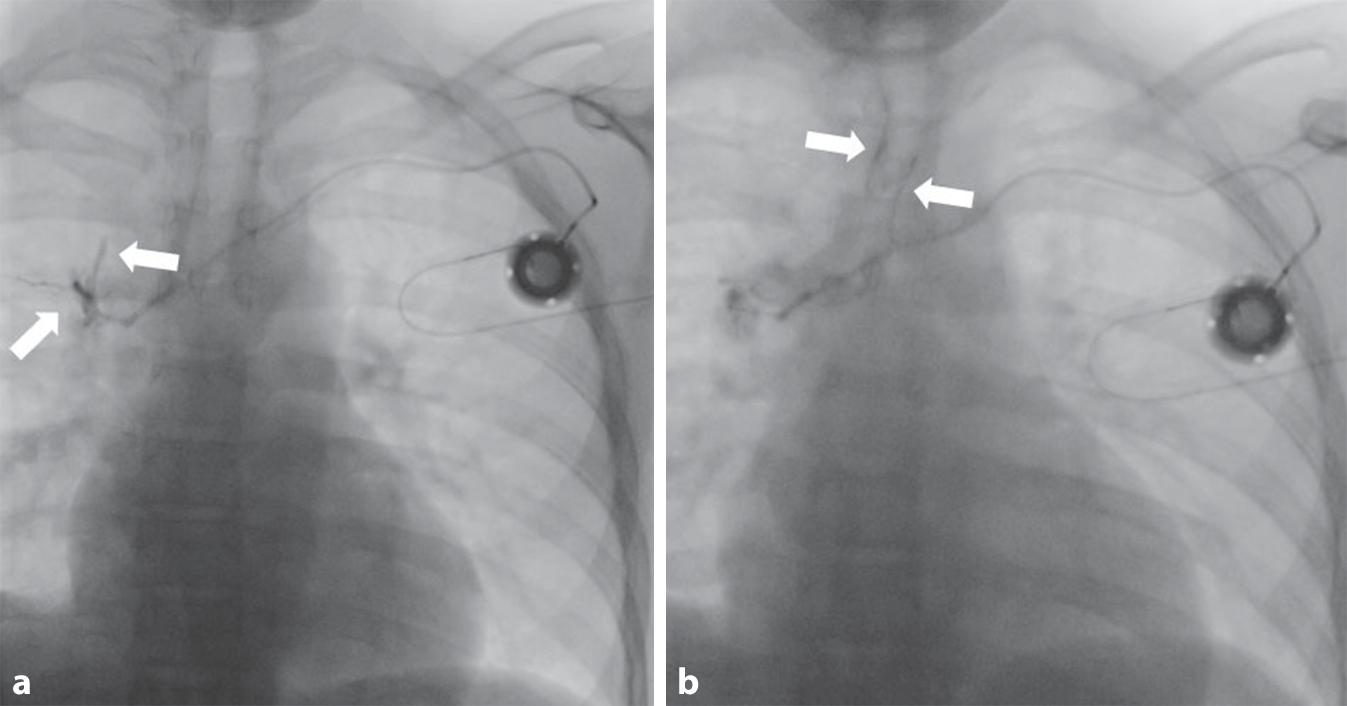

In der ergänzenden kontrastmittelgestützten Computertomographie (CT) zeigte sich ein Thrombus in der Vena cava superior (VCS) um die Portkatheterspitze. Die Portkatheterspitze schien knapp außerhalb der VCS zu liegen mit umgebendem Hämatom (Abb. 2).

Abb. 2

Computertomographie (CT) des Thorax mit axialer (a) und parakoronarer (b) Rekonstruktion im Weichteilfenster. Um die Spitze des Portkatheterschlauchs ist ein Thrombus abgrenzbar (Pfeile) mit angrenzendem Hämatom. Die Spitze des Portkatheters scheint neben der Vena cava superior zu liegen